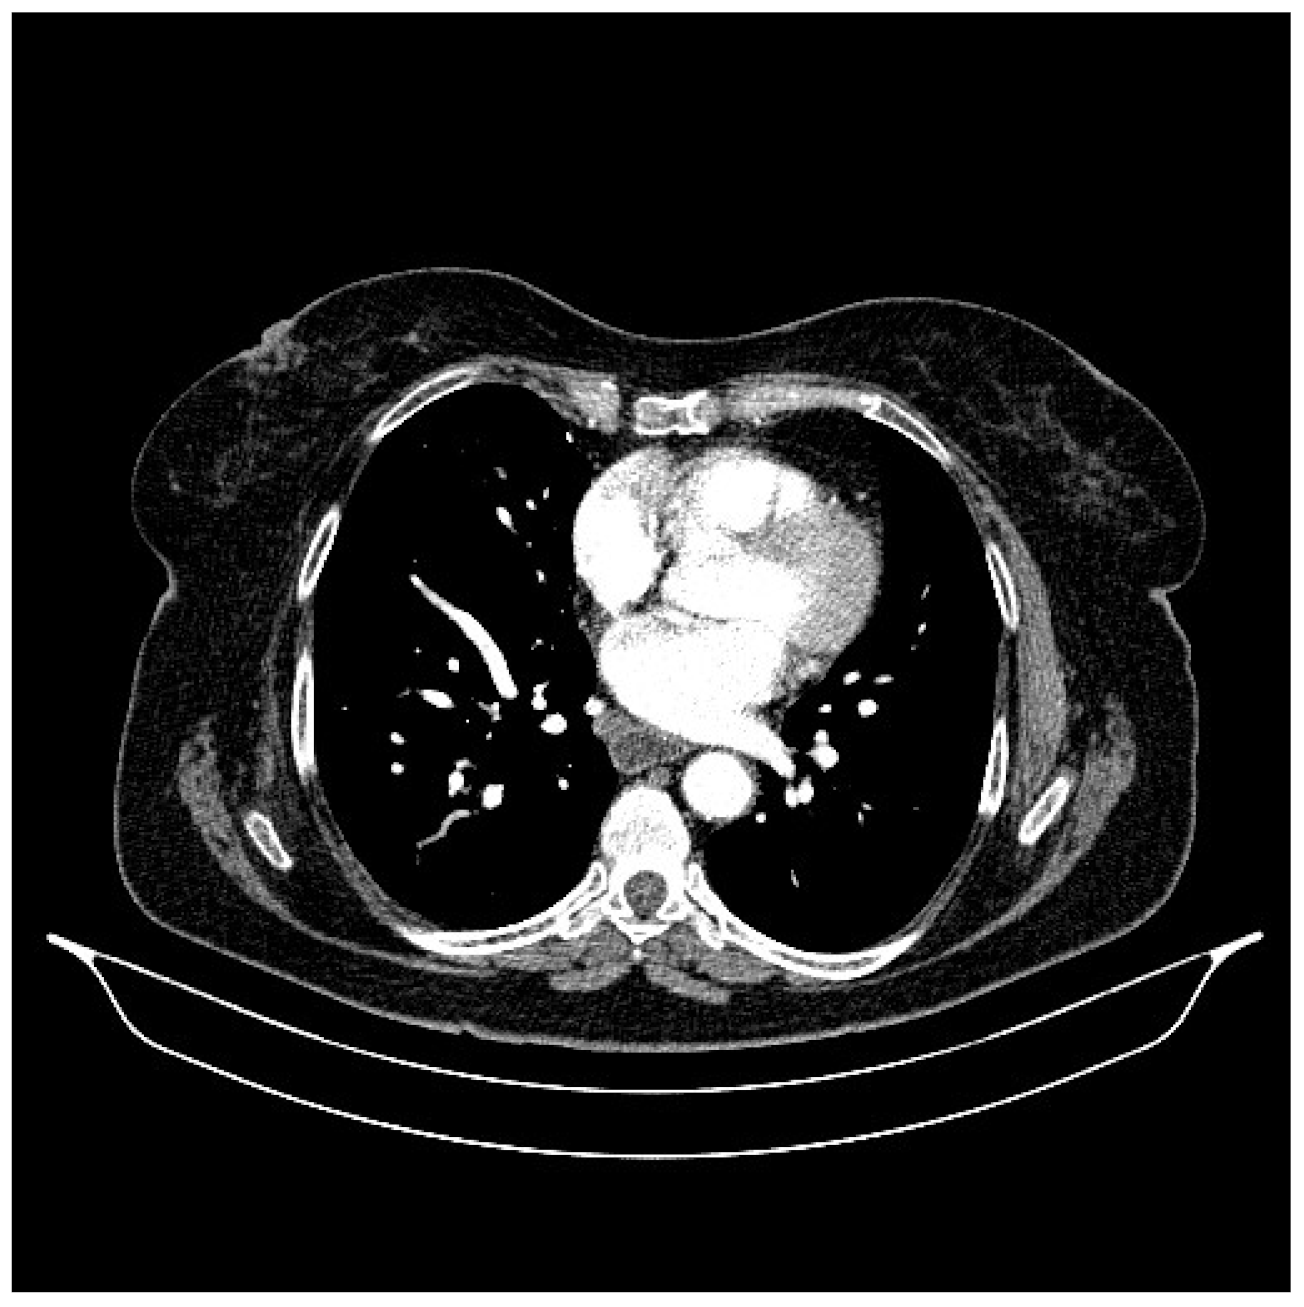

2. Case Presentation